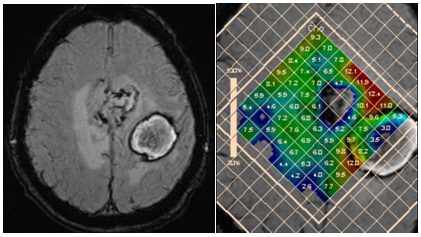

An increase of the myo-inositol level is typical for gliomas. The highest level of myo-inositol shows a relatively benign (grade II) astrocytoma. According to Riyadh et al.,45 the average value of Myo/Cr is 0.49 for benign and 0.33 to 0.15 for anaplastic glioblastoma.45,46 Spectroscopy also provides clinically valuable information for planning stereotactic biopsy (Figure 18), in evaluation of perifocal areas after invasive tumor removal, for radiation therapy planning (Figure 19), and in discrimination between radionecrosis and tumor recurrence (Figure 20). In all these cases, the highest concentration of choline (Cho/NAA and Cho/Cr ratio) is estimated.

Figure 18 Bilateral thalamic astrocytoma. PRESS, TE 30 ms (a) and PRESS, TE 135 ms (b) and map of myo-inositol (c) and choline (d) concentrations, for planning stereotactic biopsy. Histological analysis revealed anaplastic astrocytoma, though high myo-inositol concentration is more typical for grade II gliomas.

Figure 19 Maps of Cho concentrations in patients after removal of anaplastic astrocytoma without evidence of tumor invasion (a), and glioblastoma, with evidence of tumor invasion in the perifocal area (b).

Figure 20 Partial removal, and radiation therapy of glioblastoma of the right hemisphere PRESS, TE 135 ms (a) and concentration Cho map (b). Tumor recurrence is evident in the opposite hemisphere.

In the differential diagnosis between radionecrosis and recurrent glioma, it is important to remember that during 4 months after irradiation brain parenchyma may exhibit high levels of choline.47 According to Schlemmer et al.,48 for recurrent tumor average values are: Cho/NAA 3.44, Cho/Cr 2.30, while for areas of necrosis: Cho/NAA 1.29, Cho/Cr 1.26.48

Most authors agree that the examination of the peritumoral zone has greater value for differential diagnosis.52,53 Unlike glioblastomas, ration of Cho/NAA and Cho/Cr in the peritumoral area of metastases is close to those in normal parenchyma (Figure 21).

Figure 21 Two hemorrhagic foci in the left hemisphere; discrimination between glioblastoma and metastasi. SWI (a) and concentration Cho map (b). High choline levels in peritumoral area are in favor of multifocal glioblastoma.